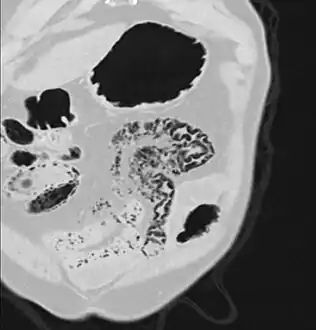

Pneumatosis intestinalis at computed tomography in intestinal ischemia. Lung window for better representation of the gas deposits in the intestinal walls. Coronal reconstruction.

Pneumatosis intestinalis in the coronal computed tomography in lung window. It can be seen next to gas entrapment in the bowel wall and gas in the stomach wall and in numerous vessels, including the portal vein into the liver.

Pneumatosis intestinalis in computed tomography with intestinal ischemia. Lung window for better representation of the gas deposits in the intestinal walls.